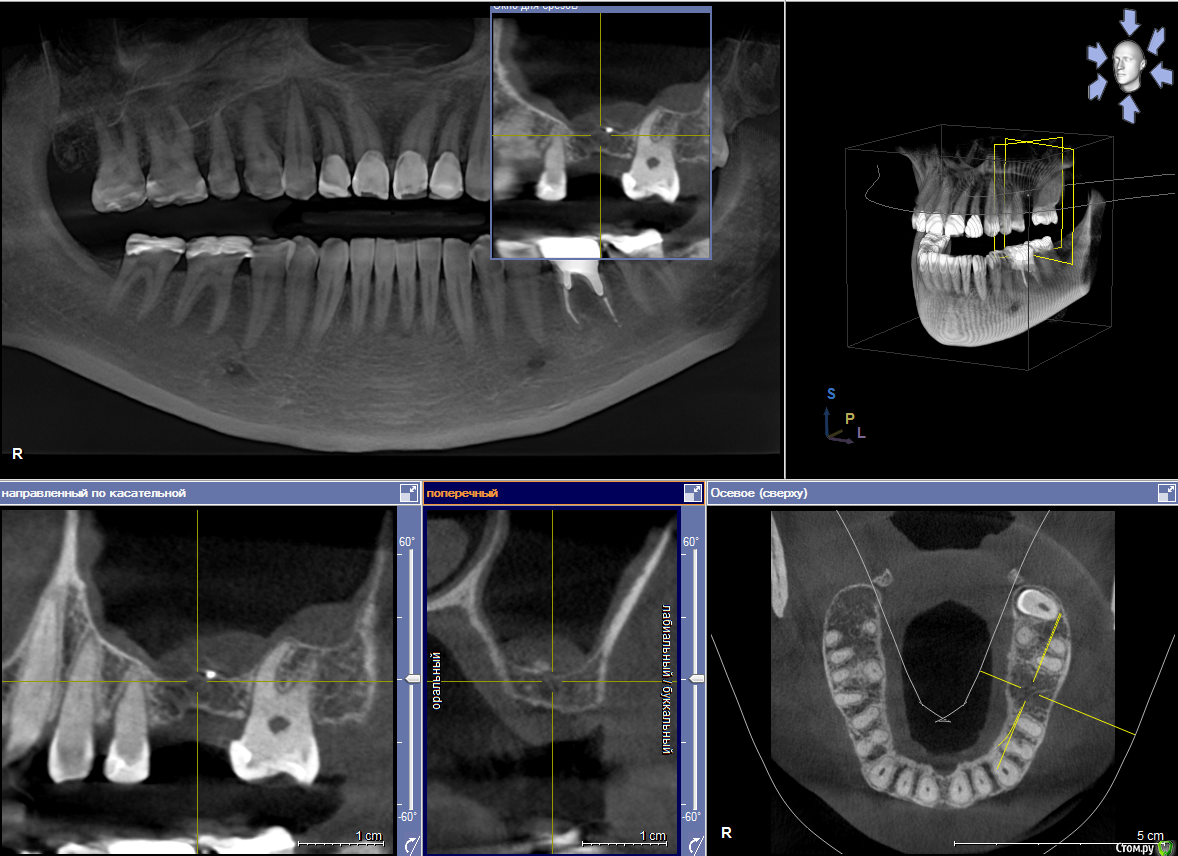

Dmitry DK Опубликовано 10 сентября, 2019 Поделиться Опубликовано 10 сентября, 2019 Фотопротокол к сожалению не полный, но ничего особенного и не проводилось. 1) Открытый синус, удален пломбировочный материал из пазухи, уложен 1 г Bio-oss 2) через 6 мес имплантация Straumann SP 4.1\10 Результат через год 9 Ссылка на комментарий